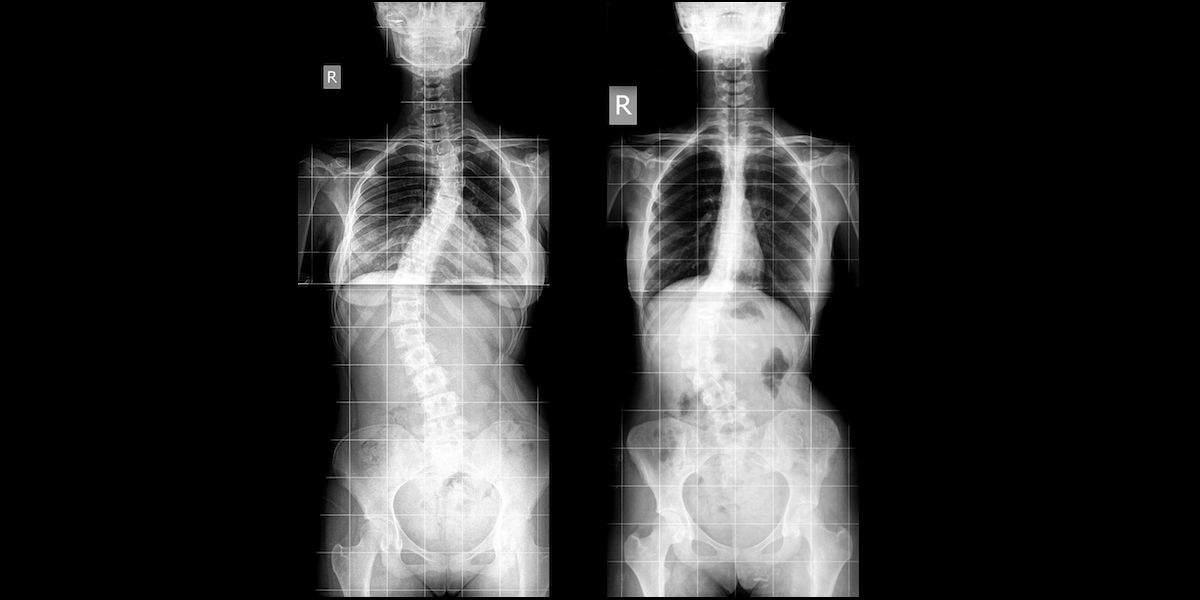

Skoliosis adalah salah satu jenis kelainan tulang belakang. Gejala khas dari gangguan muskuloskeletal ini yaitu membuat tulang belakang melengkung ke arah samping; bisa membentuk huruf S atau C. Selain itu, skoliosis juga bisa menimbulkan rasa tidak nyaman atau nyeri punggung. Lantas, apa saja cara untuk menyembuhkan penyakit skoliosis? Yuk, lihat daftar pengobatan skoliosis berikut ini.

Kelengkungan tulang belakang bisa membentuk huruf S atau C. Pola kelengkungan huruf S ini cenderung progresif dan lebih buruk kondisinya ketimbang pola huruf C.